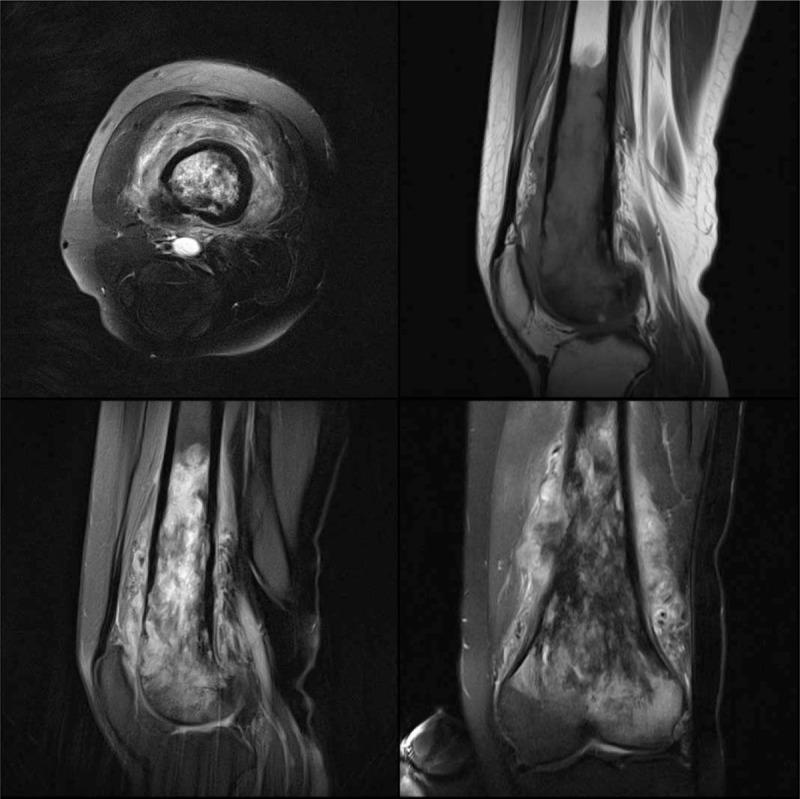

PATIENT CONCERNS

A 25-year-old female patient was consulted in the Armed Police General Hospital (Beijing, China) due to repeated pain in the right thigh lasting over 1 year. Imaging examination revealed a space-occupying lesion in the right femur.

骨促结缔组织增生性纤维瘤(DFB)是一种极为罕见的良性骨肿瘤,可发生于任何骨骼,可见于任何年龄段。在此,我们报告一例具有非特异性影像学表现的病例。

患者情况

一名25岁女性患者因右大腿反复疼痛超过1年就诊于武警总医院(中国北京)。影像学检查发现右股骨有占位性病变。